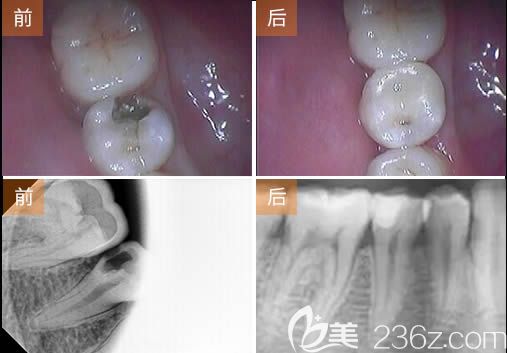

张婉瑜医生根管治疗牙髓病案例展示:

顾客:刘先生,27岁;

牙齿问题:牙齿龋坏、牙髓炎;

治疗方案:根管治疗术+树脂补牙;